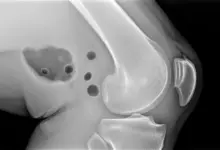

O entesófito é uma formação óssea que surge no ponto de fixação de tendões ou ligamentos no osso, que pode aparecer como resposta a tração repetitiva, desgaste progressivo, inflamação crônica ou alterações mecânicas do joelho.

O entesófito é uma projeção óssea formada na entese, que é o local onde tendões, ligamentos ou cápsula articular se prendem ao osso. No joelho, pode acontecer em regiões como:

Esse achado pode estar ligado ao envelhecimento articular, a processos inflamatórios de longa duração, à tração excessiva do aparelho extensor e até a alterações de alinhamento do membro inferior.

Em alguns pacientes, ele é apenas um sinal radiográfico. Em outros, participa do quadro doloroso de forma direta.